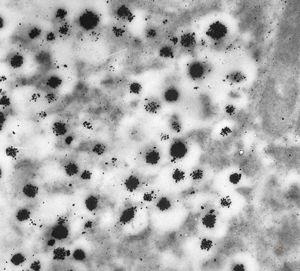

M, 62y. | pheochromocytoma